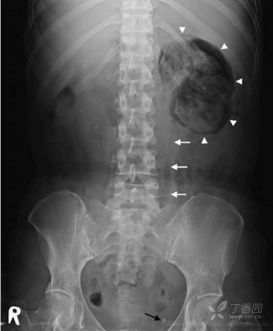

辅助检查:血常规:白细胞 19.89 ×10^9/L、中性粒细胞百分比 90.80 %、血红蛋白 92g/L、快速-CRP >200.0 mg/L。生化:尿素氮 12.5 mmol/L、钙 1.82 mmol/L、葡萄糖 17.98 mmol/L,肌酐520umol/L;肝功能:天门冬氨酸氨基转移酶 148 U/L、r-谷氨酰转移酶 253 U/L、碱性磷酸酶 190 U/L、5'-核苷酸酶 15.40 IU/L、直接胆红素 11.8 umol/L、总蛋白 50 g/L、白蛋白 21 g/L、总胆汁酸 10.2 umol/L、胆碱脂酶 2440.0 U/L;心酶三项:乳酸脱氢酶 1349 U/L。肌红蛋白,CK-MB 正常。肌钙蛋白-I 1.26 ng/ml。D-二聚体 1.4mg/L,降钙素原 42 ng/ml.NT-proBNP 473.2pg/ml.床边心电图:窦性心动过速,ST-T改变。行泌尿系超声,超声科医生电话告知:找不到左肾了!真的找不到了!2天之间,左肾消失了?行腹部X线提示: